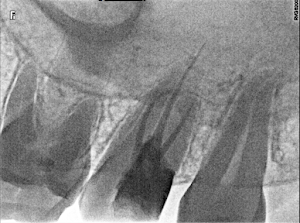

Welcome to our gallery

See how our company transforms ideas into reality. This gallery is a visual testament to our work and achievements.